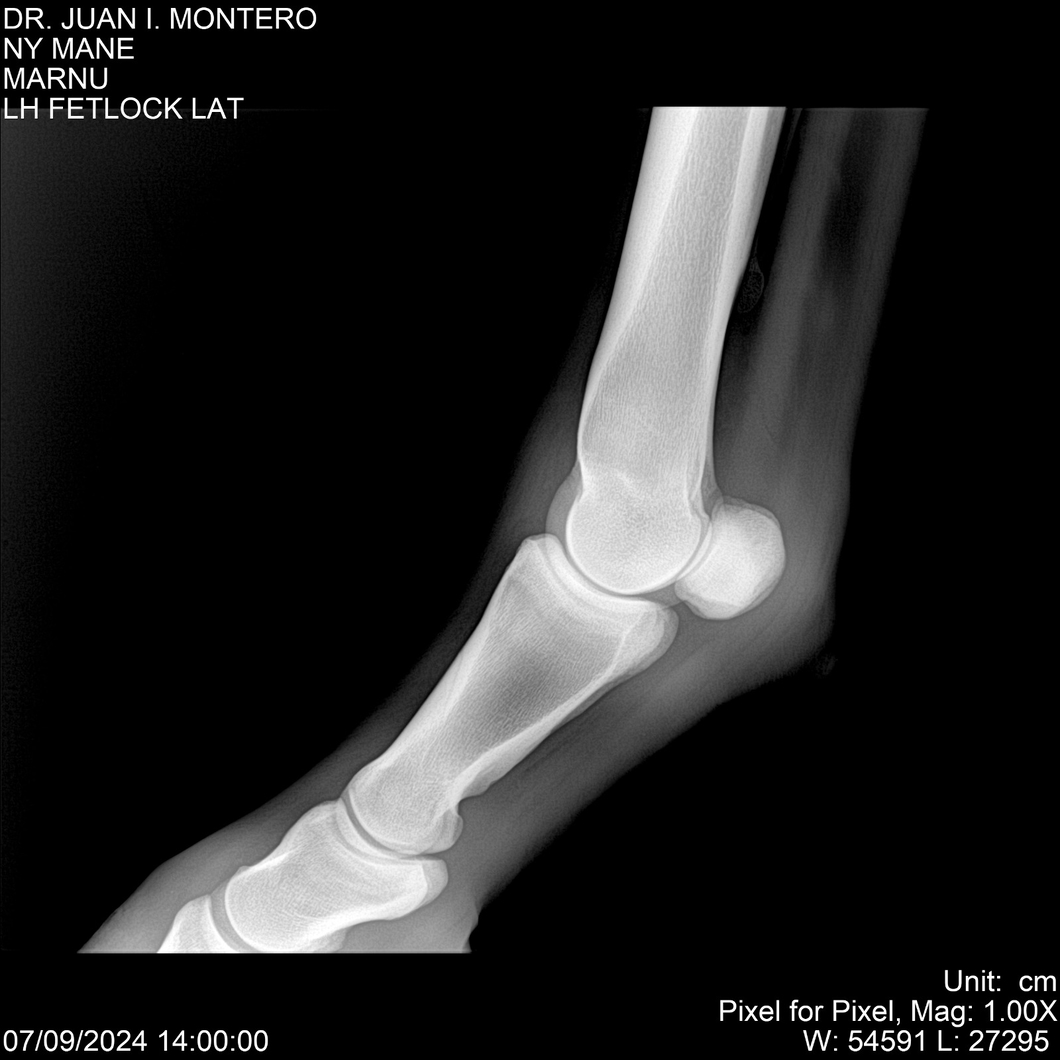

LOTE 20, NY MANE Lote Anterior Volver al remate Lote Siguiente Ficha Contacto Montevideo - Ficha del Lote Identificador: #282520 Categoría: Yeguarizos 76 Visualizaciones ClicData Contacto Empresa: Abelenda N. R., Walter Hugo Nombre*: Teléfono* : E-mail* : Mensaje Enviar Registrese gratis Este contenido Exclusivo está disponible sólo para usuarios registrados Ingresar